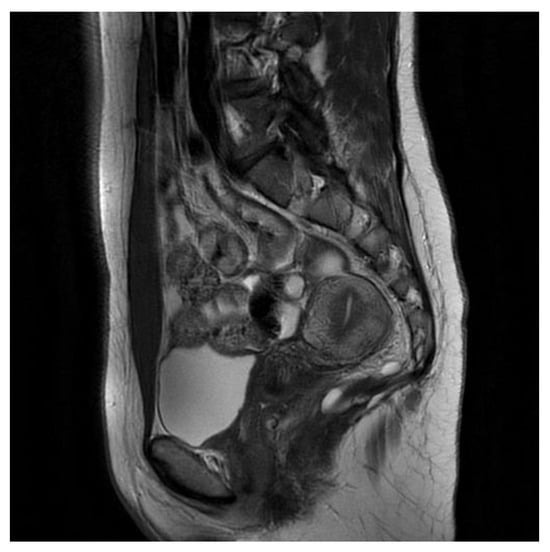

In the histopathological examination, a multilocular, cystic tumor was described. In the wall, fibrous tissue and smooth muscle tissue were visible. Cystic spaces were padded with cuboidal epithelium and stratified squamous epithelium without signs of cell atypia. Malignant transformation was excluded and the tailgut cyst diagnosis was favored [Figure 2].

Figure 2. First patient histopathological examination. (a) Tissue at 4× magnification. (b) Tissue detail at 10× magnification.